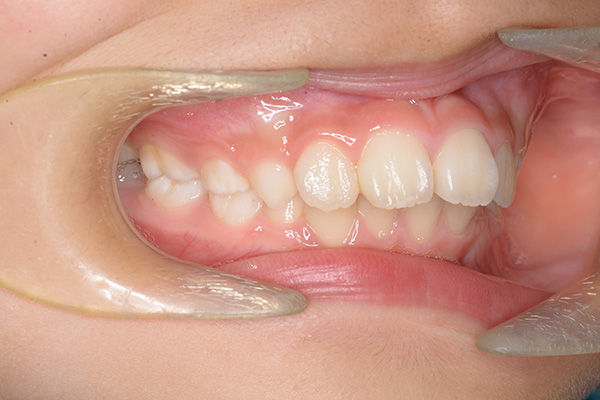

初診時

FP・IOP

主訴 出っ歯 診断名 アングルⅡ級1類

初診時年齢 7歳0ヵ月 性別 動的治療期間 28ヵ月

口腔内所見 over jet 7.5mm,over bite 3.5mm,大臼歯関係はⅡ級 。Hellmanのdental ageはⅢAであり上突咬合を呈していた。